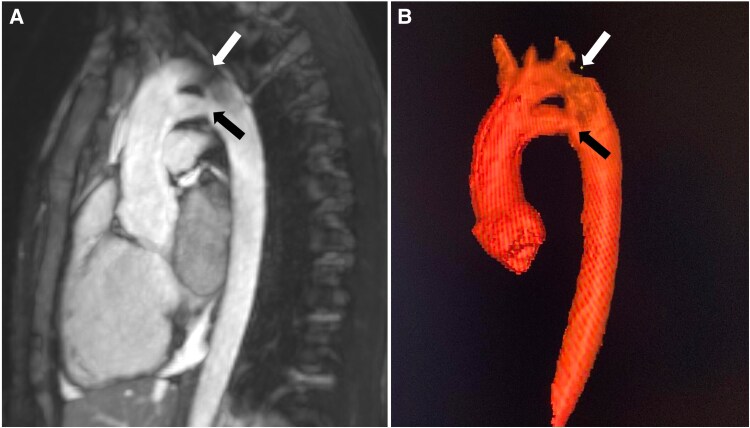

First case of isolated persistence of the fifth aortic arch observed on magnetic resonance imaging.